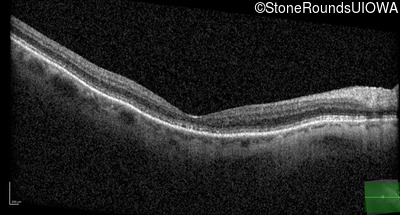

Optical Coherence Tomography - Right - 20/300

Exemplar / OCT Stack

Optical Coherence Tomography - Left - 20/150